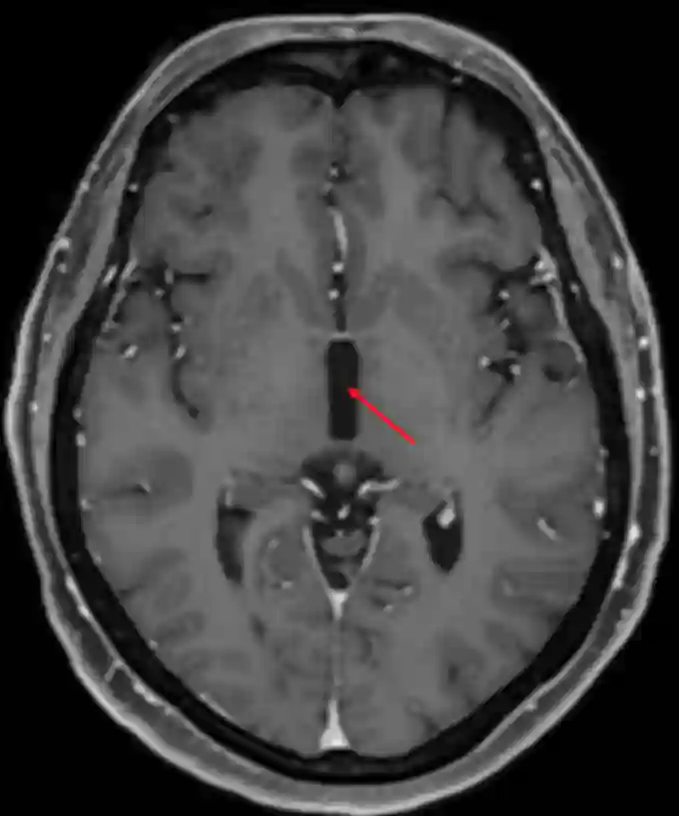

Dritter Ventrikel im axialen MRI

Dritter Ventrikel im axialen MRI in einer T1 Kontrastmittelsequenz.